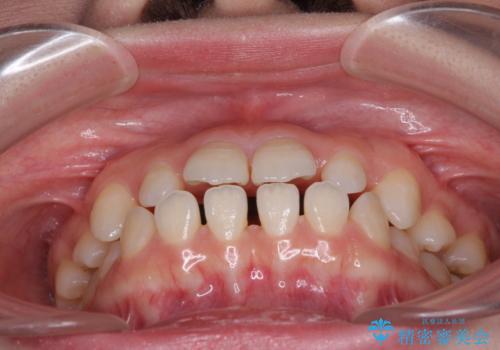

- 歯の欠損による隙間だらけの歯並びを気にして来院された患者様です。

上顎左右1本ずつ欠損していたため、歯列矯正により欠損部位にスペースを集め、その後欠損部位をインプラントにて補綴することとしました。

インビザラインによる矯正治療も提案しましたが、長時間の装着や自己管理が難しいとお考えで、ワイヤーによる矯正治療を行いました。

歯並びは比較的早めに整いましたが、インプラントを埋入するにあたって前後の歯根位置を改善する必要があり、矯正治療に期間を要することとなりました。